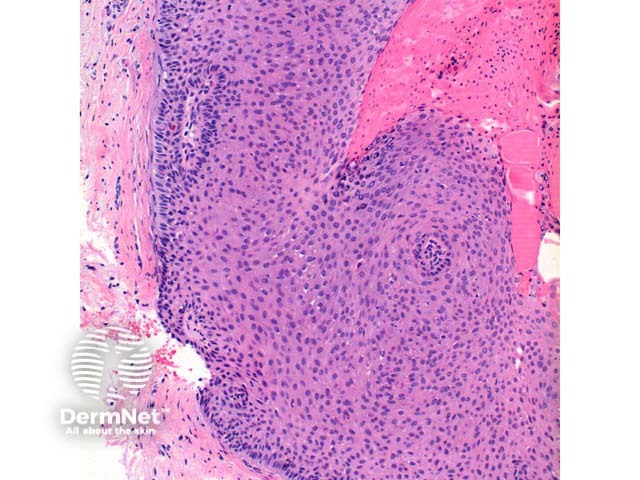

In pilar sheath acanthoma, there is a lobular proliferation of benign squamous epithelium in the dermis (figure 1, 2). These lobules surround small cystic spaces. The lining cells may have a granular layer similar to an epidermoid cyst (figure 3) or have an attenuated granular layer similar to a trichilemmal cyst (figure 4).

The lobules are composed of bland keratinocytes and are surrounded in areas by an eosinophilic basement membrane. There are often areas of clear cells (figures 5, 6). These features indicate outer root sheath differentiation.

Figure 2